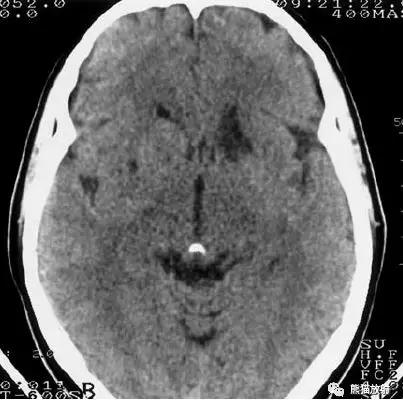

上矢状窦血栓形成,呈高密度(箭头);并邻近脑实质内出血性脑梗死。